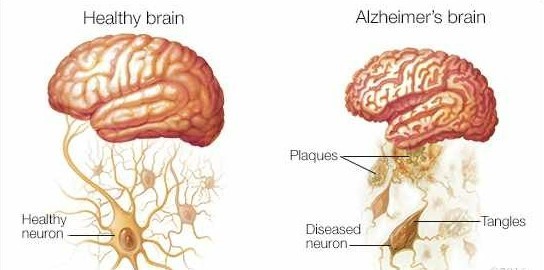

FDG-PET study with late-onset (upper) vs. early-onset (lower) Alzheimer Disease

Most patients with Alzheimer disease are older adults, while it can also afflict individuals in their 30s or 40s. Early-onset (or younger-onset) Alzheimer disease is the term used to describe the disease that develops in people under the age of 65.

The early-onset variant of Alzheimer’s affects a relatively small percentage of people. When the condition begins to spread, many patients are in their 40s and 50s.

MRI of 3 mutation carriers and non-carriers with a predominant mutation PSEN1 p. Met146Ile.

13% of familial early onset Alzheimer disease instances are autosomal dominant, affecting at least three generations. Most Alzheimer’s cases tend to be complicated, involving numerous susceptibility genes and environmental variables.

Although the lifetime risk of the disease is about twice as high for first-degree relatives of individuals with late-onset disease, the pattern of transmissions is rarely consistent with Mendelian inheritance.